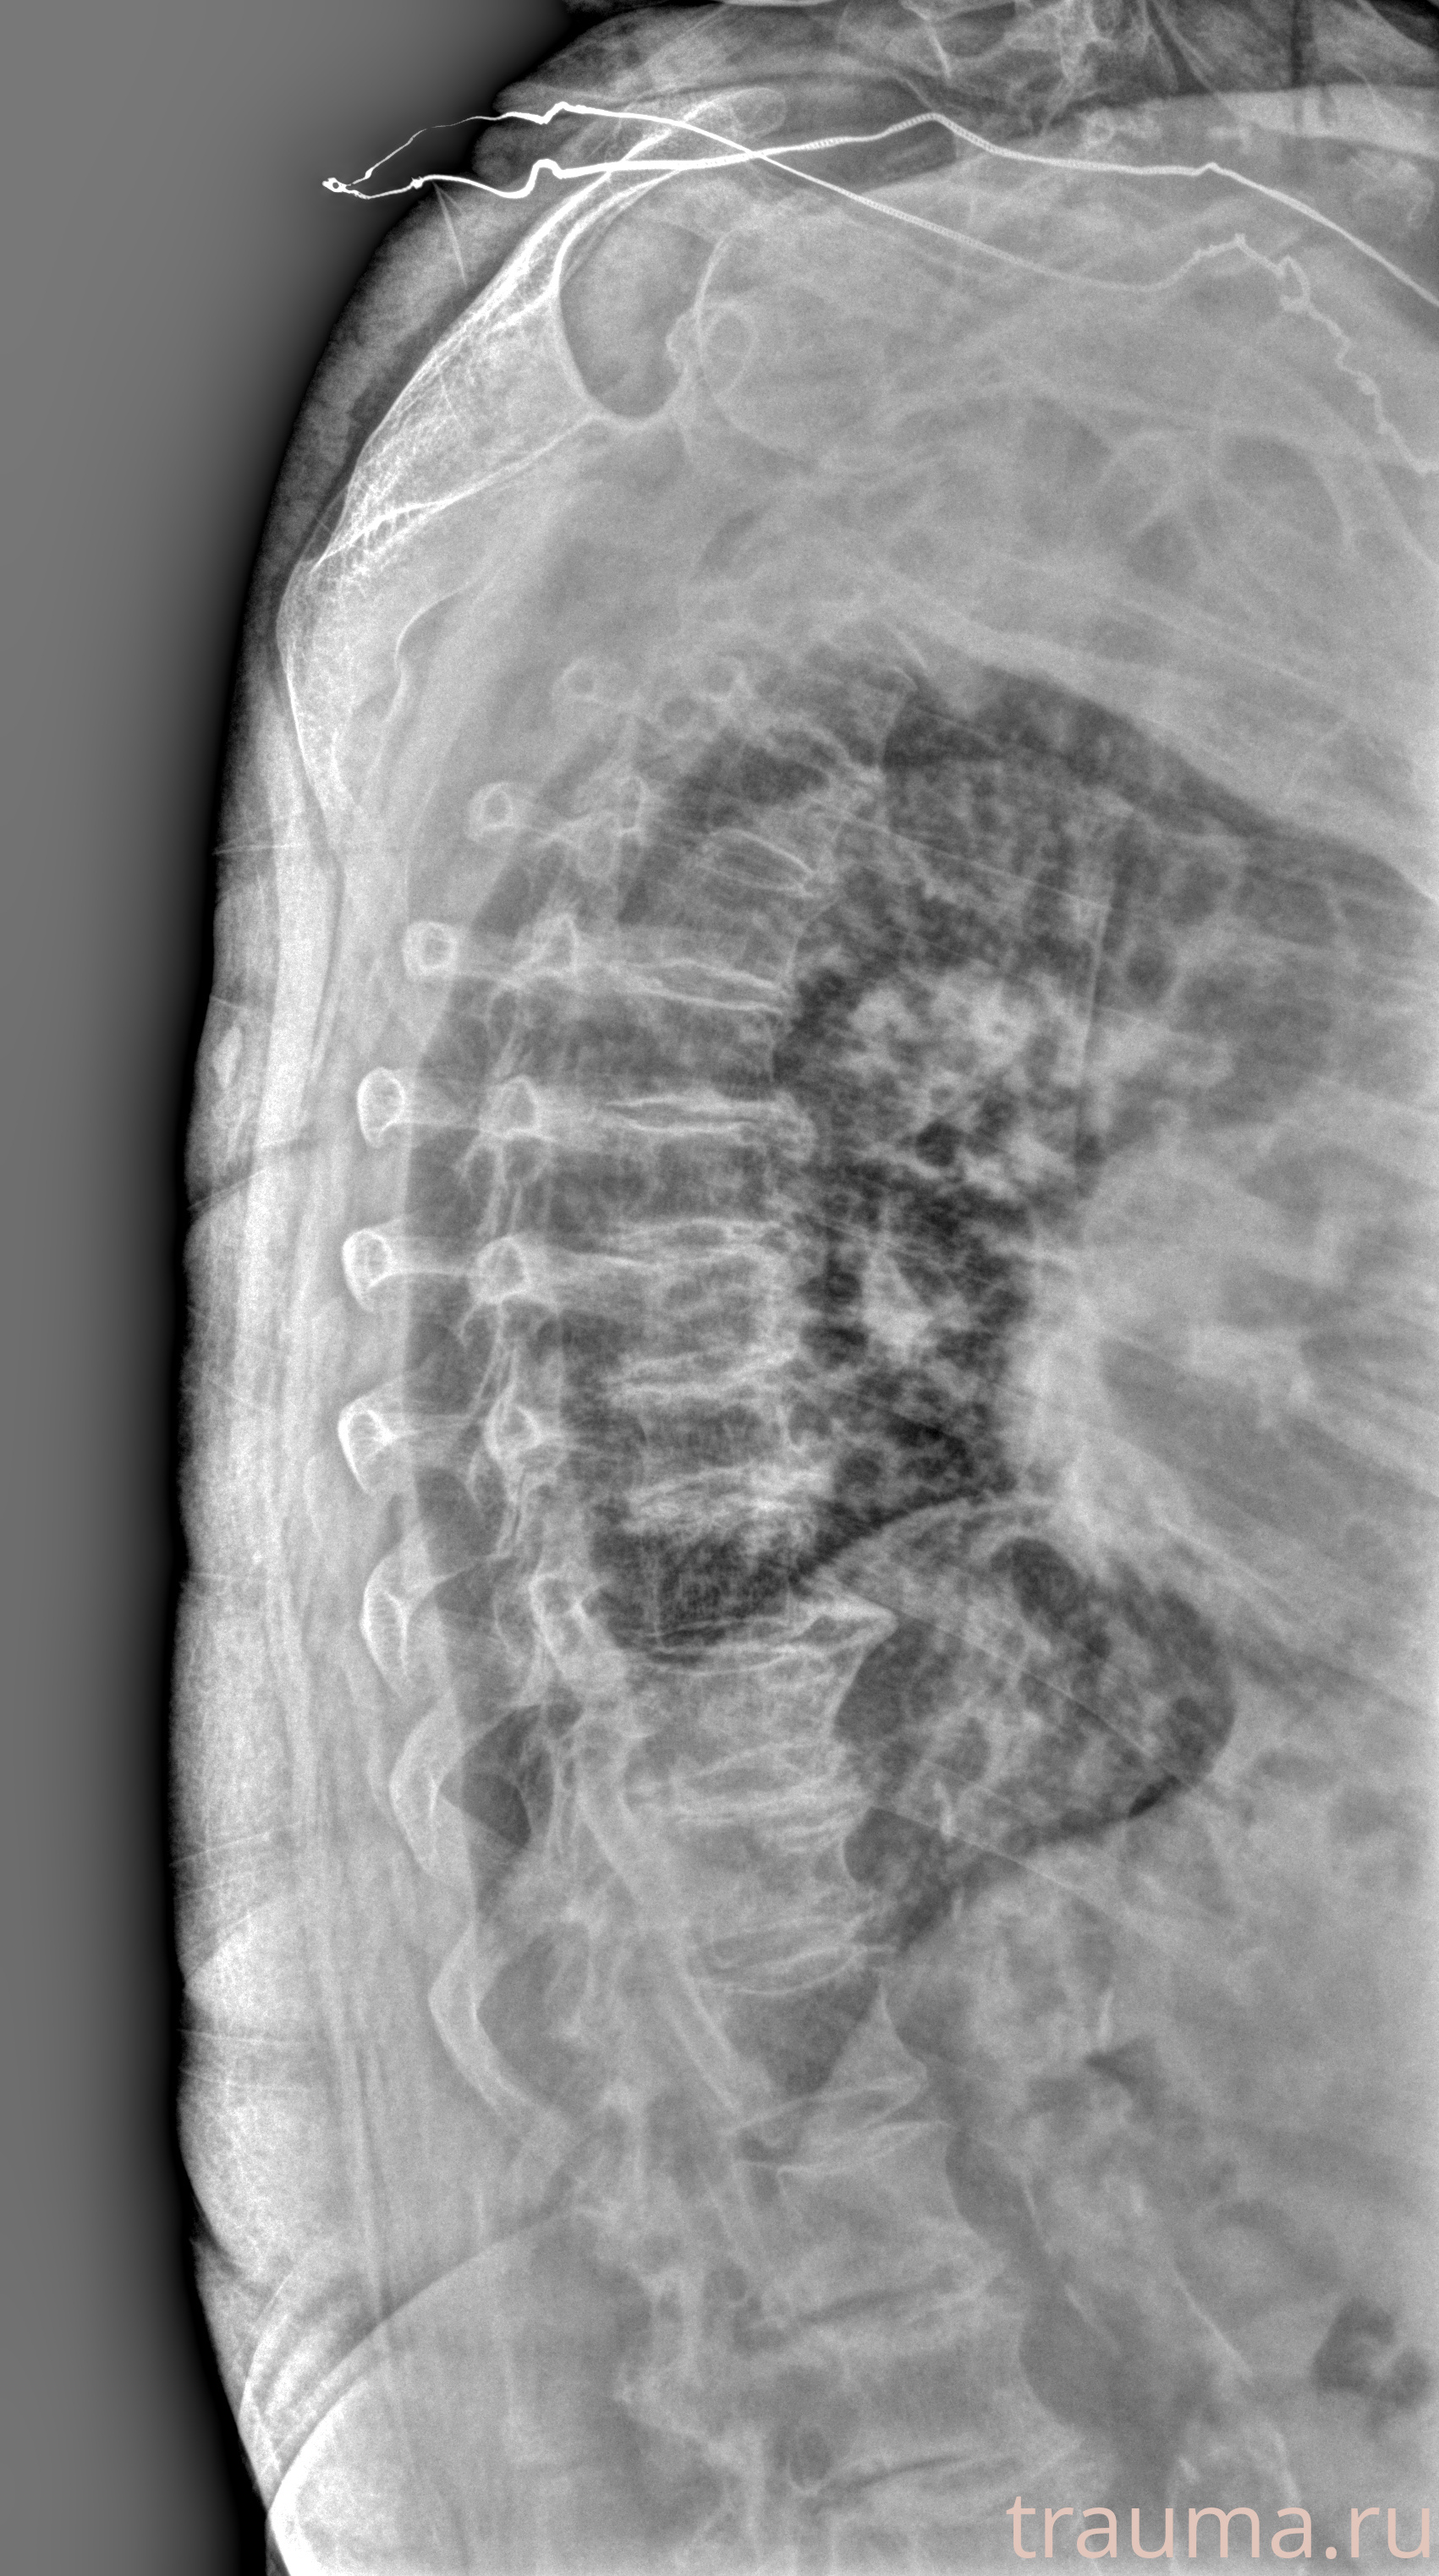

Рентген на дому: по вашему адресу приезжает врач-рентгенолог, травматолог-ортопед с мобильным рентгеновским аппаратом, проводит диагностику травмы или заболевания, делает необходимые рентгенограммы, дает рекомендации по дальнейшему лечению. Получить качественные снимки в домашних условиях возможно благодаря уникальной методике, разработанной МосРентген Центром для института  Склифосовского